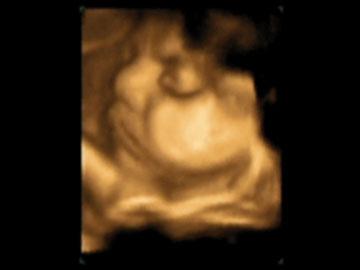

Videos de ecografías 5D HD

Para ver los videos haga click en las imágenes